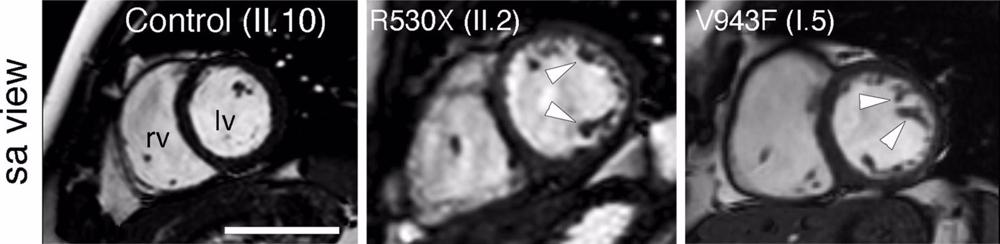

Usando estos modelos animales descubrieron que estos ratones mutantes padecían miocardiopatía no compactada del ventrículo izquierdo, pero únicamente si eran portadores de dos alelos mutantes para Mib1.

Es decir, tal y como explica el doctor De la Pompa, «se trataba de una situación distinta de la observada en pacientes, en los que la enfermedad se manifiesta en presencia de una única versión mutante de MIB1». «Además, los ratones mostraban defectos en las válvulas cardíacas, o ambas anomalías a la vez», añade.

El equipo verificó estos datos usando un modelo de ratón. «La introducción del conjunto de mutaciones identificadas en una de las familias provocó defectos en el desarrollo de las cámaras cardíacas, causando LVNC y afectando a la función del corazón. Además, el otro grupo de mutaciones causó defectos valvulares a los ratones portadores, lo que mostró que estas nuevas variantes funcionaban como modificadores del efecto de la mutación en Mindbomb1», ha señalado Marcos Siguero Álvarez.